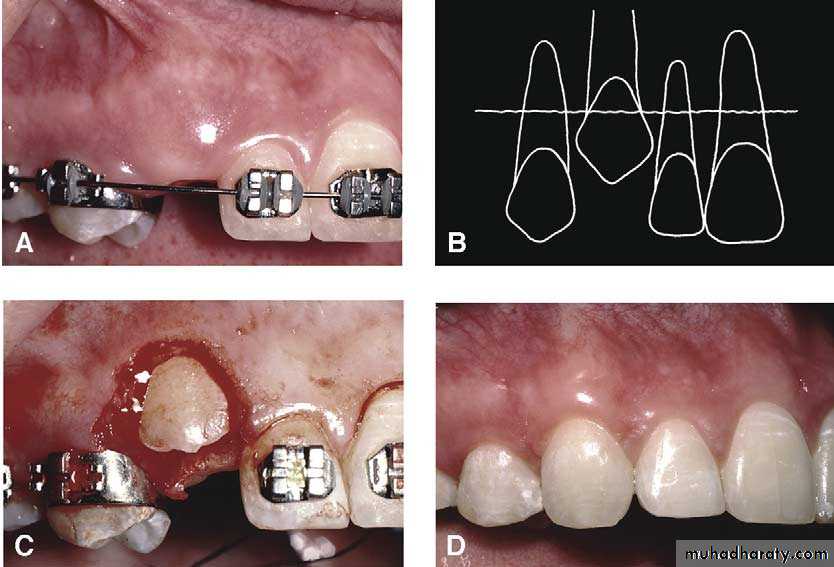

Surgical exposure :the path of eruption is not obstructed

Surgical exposure with orthodontic traction: the path of eruption is obstructed

Surgical exposure with orthodontic treatment (palatal approach )

The initial stage of the operation is to reflect the mucoperiosteum and to remove the bone overlying the tooth to expose the greatest coronal diameter, the incisal edge and the cingulum .

before repositioning the palatal flap a window is excised in it corresponding to the bony cavity containing the crown .the flap is then sutured as usual and a pack of iodoform gauze should be pressed firmly in to the bony defect so as to cover the exposed crown .

This pack should be held in position with suture and left insitu for 2-3 weeks to prevent granulation tissue and mucosa from overgrowing the denuded crown .after removal of the pack the progress of eruption should be observed at frequent intervals .

Following exposure of the tooth , orthodontic treatment may be required to guide it into a good position in the arch . Some times orthodontic traction is arranged at the time of surgery .